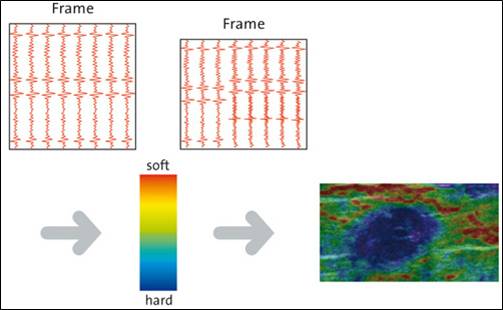

Die Echtzeit-Elastographie ist eine Messung der Elastizität des Prostatagewebes. Dies ist ein bildgebendes Verfahren, mit dem tumorverdächtiges Gewebe in der Prostata mittels verschiedenen Farben auf dem Ultraschallmonitor angezeigt wird. Dabei misst die Ultraschall-Elastographie die Elastizität des Gewebes, also die Härte des Prostatagewebes indem es die Reaktion des Gewebes auf Druck misst. Tumorgewebe ist in der Regel härter als gesundes Gewebe. Die harten tumorverdächtigen Areale werden so aufgespürt und können sofort gezielt biopsiert werden. Die Ultraschall-Elastographie erzielt beim Aufspüren von Tumorbereichen in der Prostata deutlich aussagekräftigere Ergebnisse als der herkömmliche Ultraschall.

Zunächst einmal werden die bereits durchgeführten und von Ihnen mitgebrachten MRT-Bilder (1,5T-3T, mit/ohne rektale Spule, DICOM-Format) in unser Gerät eingelesen. Anschließend werden die suspekten Areale und die Organgrenzen der Prostata in der MRT-Bildgebung markiert. Nun beginnt der praktische Teil: In angenehmer Seitenlage wird über einen modernen transrektalen Ultraschall die Prostata aufgesucht und anhand der Anatomie der Prostata mit dem MRT Bild fusioniert. Der Untersucher sieht nun auf der linken Seite des Flachbildschirmes des Ultraschallgerätes das Original-MRT-Bild mitsamt des Markierungen und auf der korrespondierenden rechten Seite die Live Ultraschallbilder in denen die Markierungen der MRT-Untersuchung zu sehen sind. Die auffälligen Areale können nun einer Elastographie oder einer Kontrastmittel-Untersuchung unterzogen werden um den Grad der Auffälligkeit zu bestimmen. Auf Wunsch können auch jetzt gleich die Biopsien durchgeführt werden.